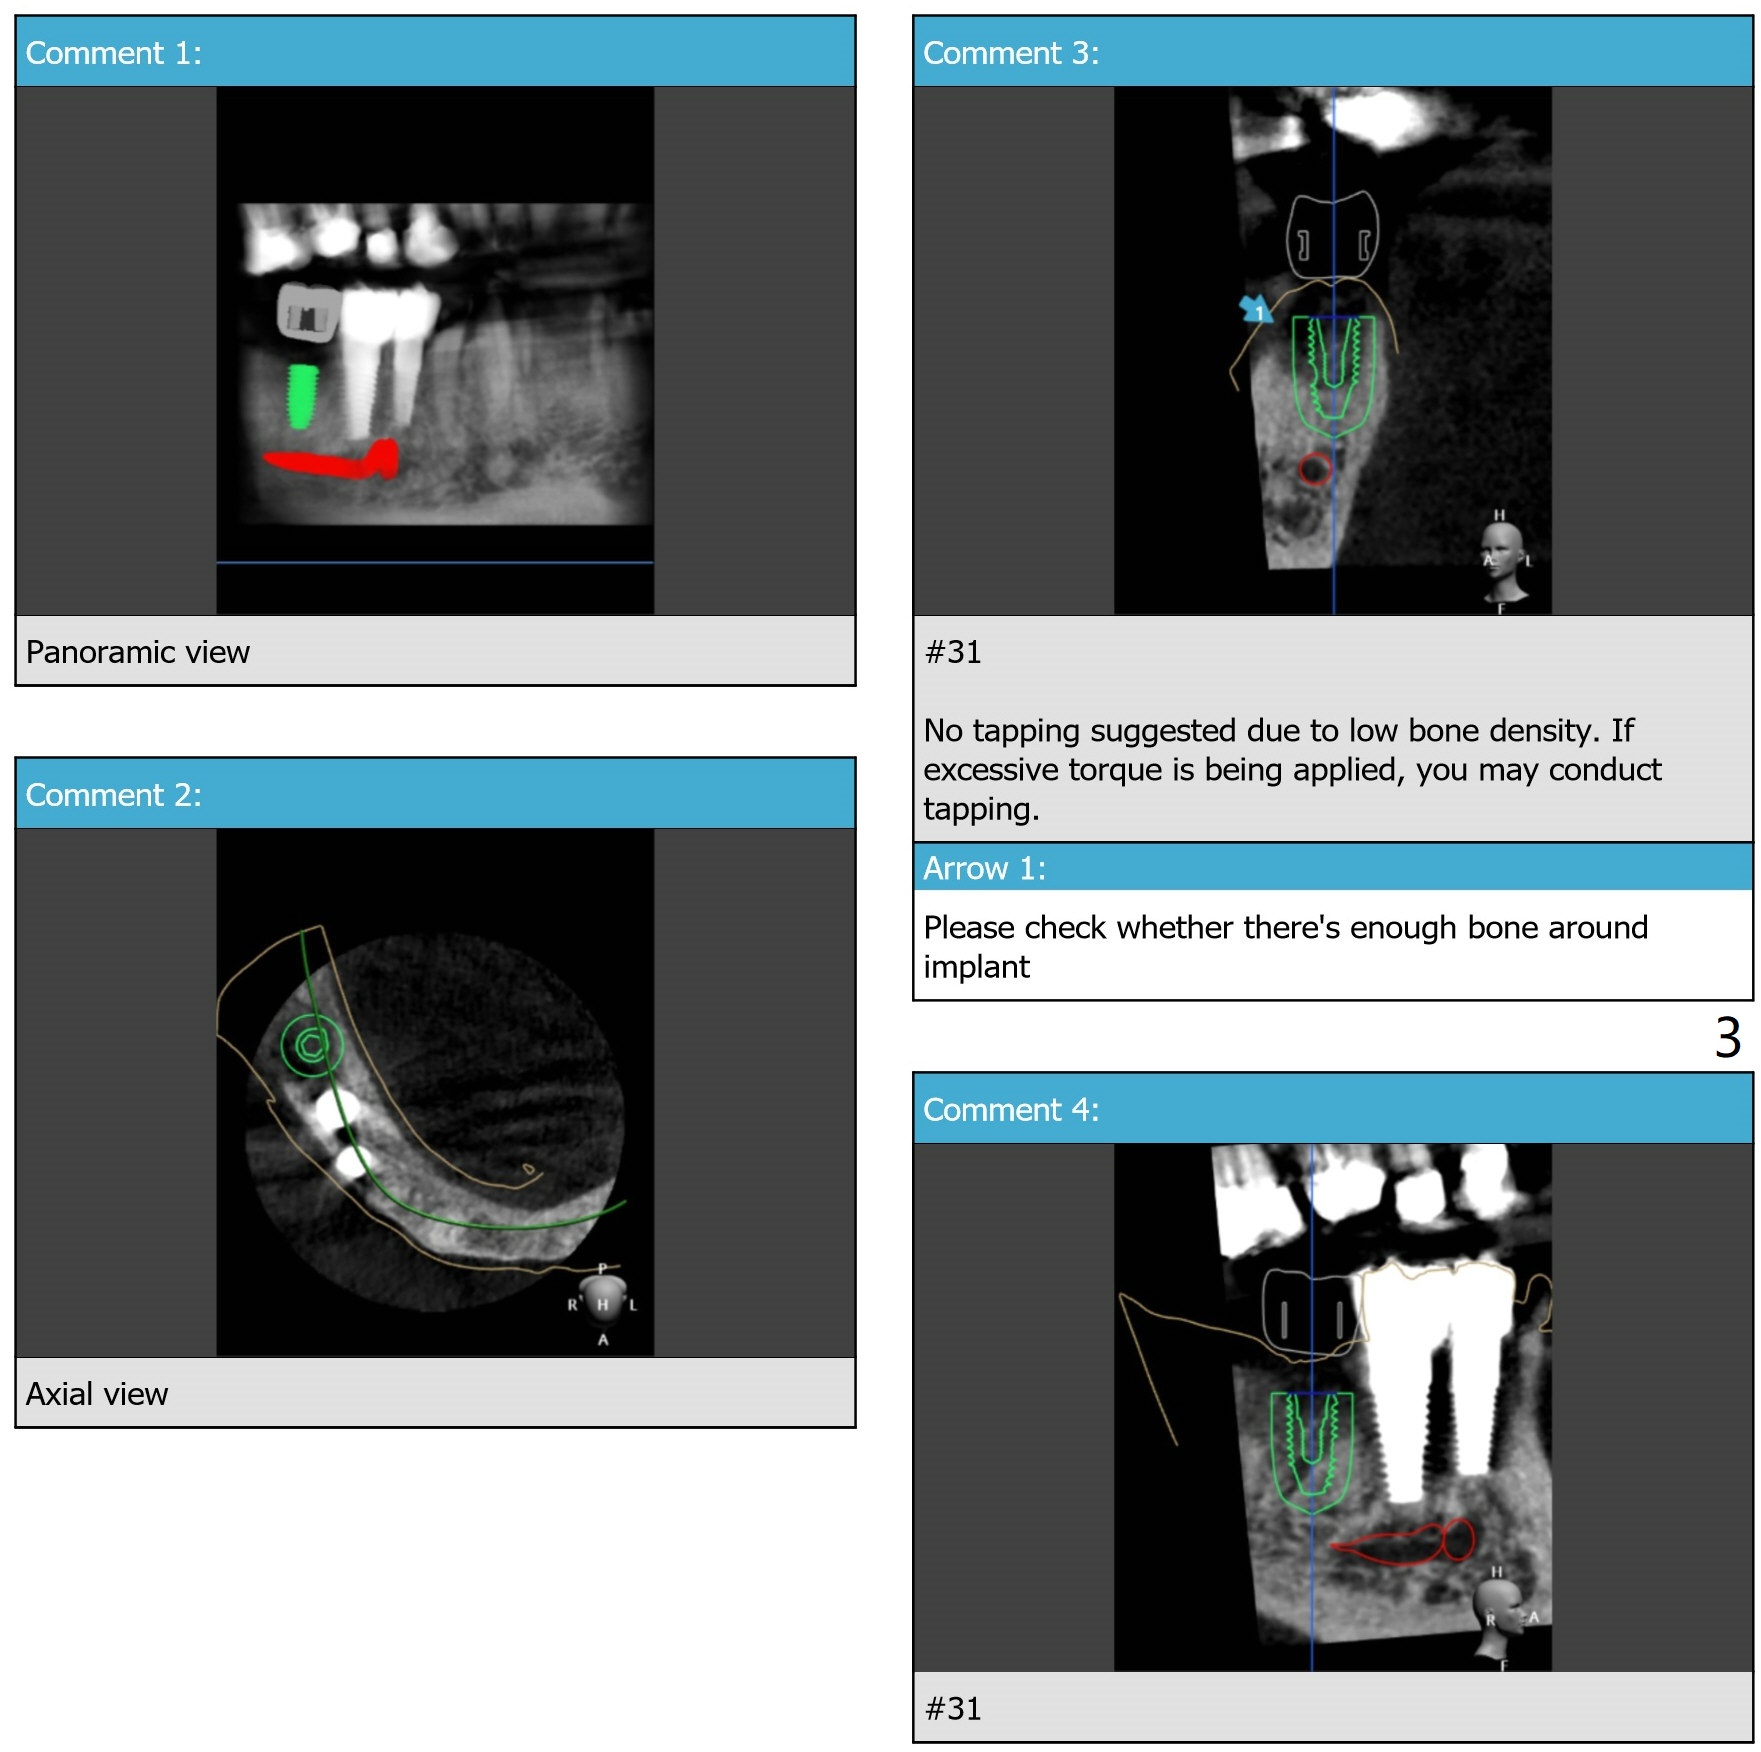

Guided surgery will be scheduled 6 months post socket preservation at #31 (Fig.1). The bone density is low buccal to the recipient site (Fig.2). Either bone expansion should be done prior to implant placement or bone graft is needed post placement (Fig.3). Use Implant Cassette and #15 may be utilized to check whether bone graft is needed. Before soak the guide, check it against the lower model to see whether acrylic clearance is necessary for bone expansion. After 2.2x7.3 mm drill, use 2.2x8.5 and 2.2x10 mm ones (Fig.5). Switch to #2 bone expander (1.3/2.3 mm) and take PA to confirm the depth. Measure the length of the last drill and #2 expander beforehand. Continue bone expanders until #5 (3.0/4.4 mm). Expect less depth as the # of expanders increases.